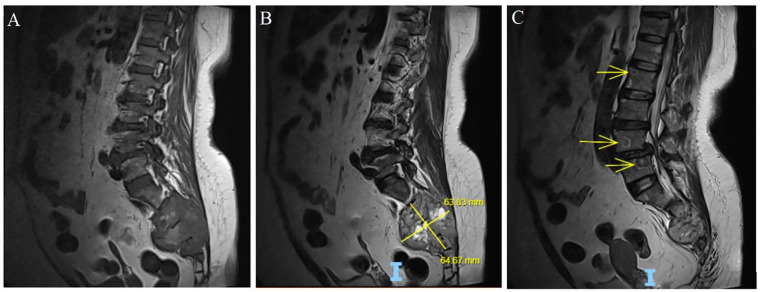

Sacral bone metastasis from primary follicular thyroid carcinoma (FTC) is rare. Most reported cases include factors indicative of thyroid origin, such as a history of treated thyroid cancer or newly identified thyroid nodules with malignant cytology. We herein report a 57-year-old woman with a metastatic sacral lesion of thyroid origin, initially misdiagnosed due to a false-negative fine-needle aspiration (FNA) cytology result of a thyroid nodule. The diagnosis was suspected based on an abnormally elevated serum thyroglobulin (sTg) level and confirmed through repeat core biopsy with thyroid-specific immunohistochemistry. This case highlights the limitations of FNA cytology in large thyroid nodules and underscores the potential role of sTg in diagnosing metastatic FTC in certain clinical scenarios. Thyroid carcinoma should be considered in the differential diagnosis of sacral metastases when the primary tumor is unknown.